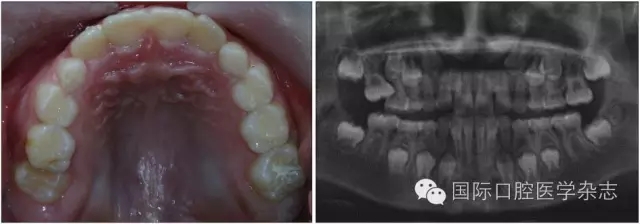

牙齒異位萌出是指恒牙在萌出過程中,未在牙列的正常位置萌出,兒童口腔臨床最常見的是上頜第一恒磨牙和上頜尖牙的異位萌出。造成第一恒磨牙異位萌出的原因包括:第二乳磨牙和第一恒磨牙的牙冠體積較大;頜骨的發(fā)育不足,尤其是上頜結(jié)節(jié)發(fā)育不足;第一恒磨牙的萌出角度異常,牙軸向近中傾斜等,歸根結(jié)底是在第一恒磨牙萌出階段出現(xiàn)了牙量和骨量不調(diào)的問題,頜骨發(fā)育不足是最主要的原因。發(fā)生率為2%~6%,男性多于女性,其中2/3發(fā)生在上頜,可單側(cè)或雙側(cè)對(duì)稱出現(xiàn)。第一恒磨牙的異位萌出常常造成第二乳磨牙早失,牙弓長度減小。臨床上,常用分牙簧分離第一恒磨牙與第二乳磨牙,或使用恒磨牙面粘著舌扣的Halterman矯治器,或變異Nance弓推第一恒磨牙向遠(yuǎn)中的方法,改變恒牙萌出道,阻斷恒磨牙對(duì)乳磨牙的壓迫吸收,引導(dǎo)恒磨牙正常萌出。圖7顯示為一左上第一恒磨牙異位萌出的患兒,左上第二乳磨牙松動(dòng),牙弓長度減少[6]。

640.webp (6).jpg

左:口內(nèi)照;右:全景片。

圖7 左上第一恒磨牙異位萌出,左上第二乳磨牙松動(dòng)

Fig 7 Ectopic eruption ofleft upper the first permanent molar, loose of left upper the second primarymolar